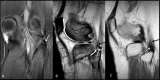

Distal biceps femoris tendon is an unusual site of calcific tendinitis and a rare cause of knee pain. We present a case of 72-year-old lady who presented with a six-month history of pain over the lateral aspect of knee. Subsequent imaging demonstrated calcific deposits within the biceps femoris tendon substance. She was then successfully treated with ultrasound-guided barbotage of the calcium deposits and peri-tendinous corticosteroid injection. Clinical awareness of the unusual sites of calcific tendinitis with imaging evidence is important for early diagnosis and appropriate management.